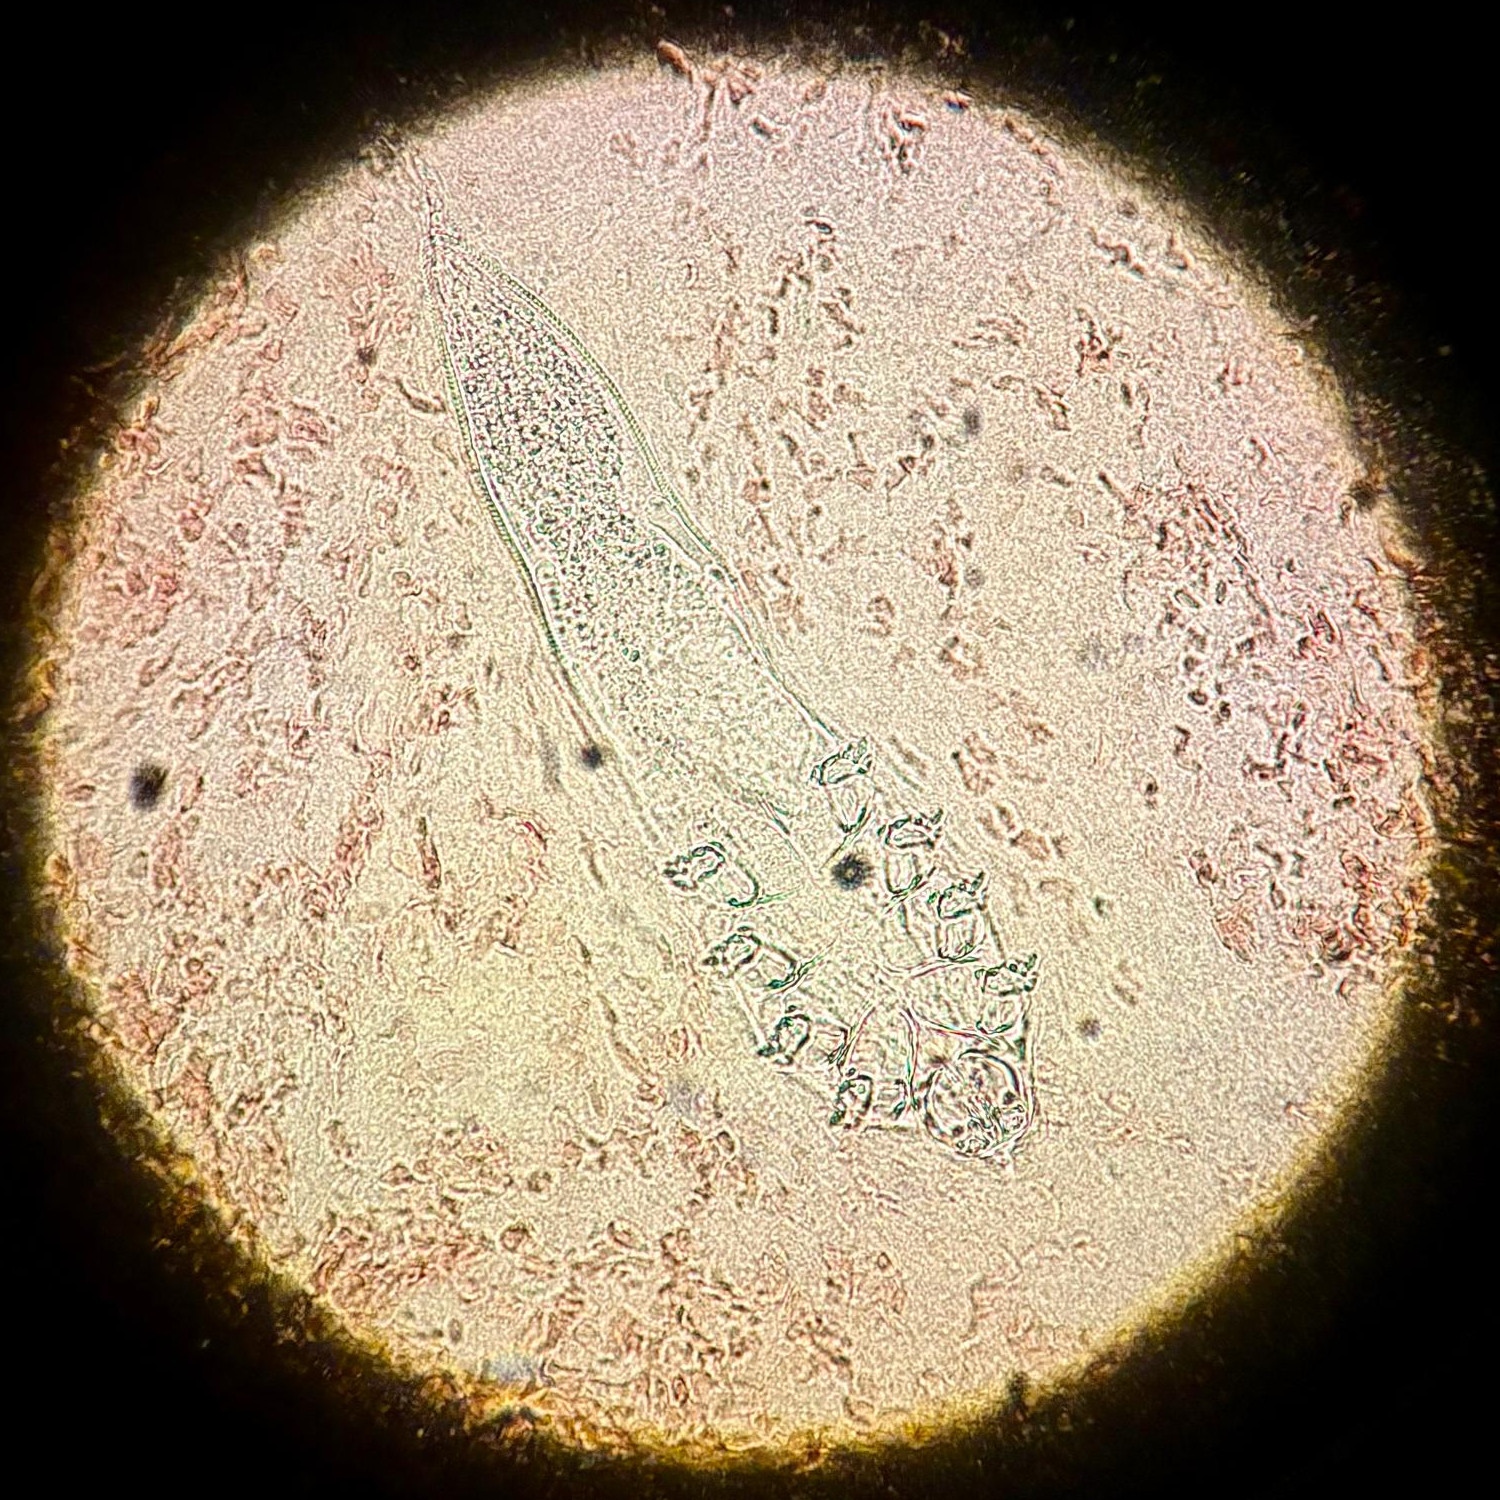

Inhoud comedo uitdrukken of haren uittrekken en onderzoeken op Demodex (in druppel NaCl onder dekglaasje). Of een stuk plakband gebruiken, omgekeerd bevestigen op objectglas en bekijken onder de microscoop. Of een biopt. De interpretatie is moeilijk omdat Demodex mijten normaal voorkomen op de huid van het gelaat. Als het er heel veel zijn, en het histologisch en klinisch beeld past niet goed bij een rosacea of bacteriële folliculitis, dan wordt de diagnose aannemelijk.

Demodex mijtDemodex mijt onder de microscoop